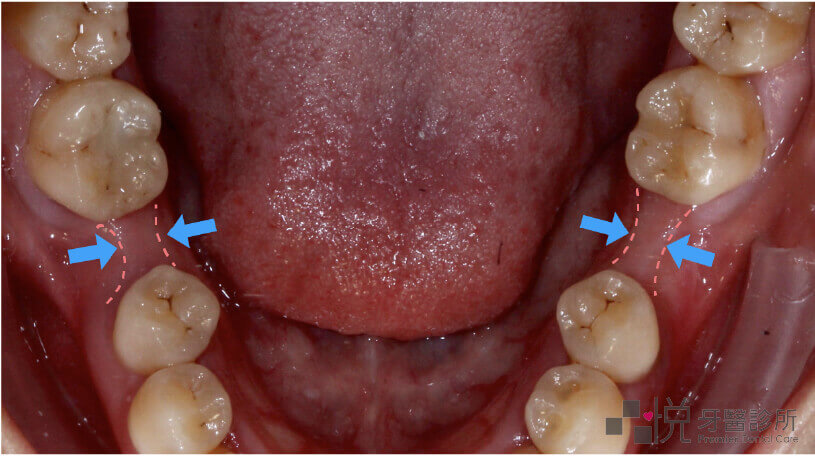

牙齒被拔除後,缺牙處的齒槽骨便會開始萎縮,寬度漸漸變窄。

單顎齒槽骨萎縮案例照片

長期缺牙的區域,齒槽骨寬度變窄

(案例照提供:錢怡雯醫師)

缺牙久牙齦萎縮拉不過去繪圖

鄰牙可能無法被拉入齒槽骨萎縮的區域

期缺牙的區域,齒槽骨可能已有相當程度的萎縮。」倘若萎縮得太嚴重,缺牙區旁邊的牙齒就無法被拉入齒槽骨萎縮的區域,因為通道太窄而無法通過。

因此,缺牙的時間愈長,愈難將缺牙空間完全關閉